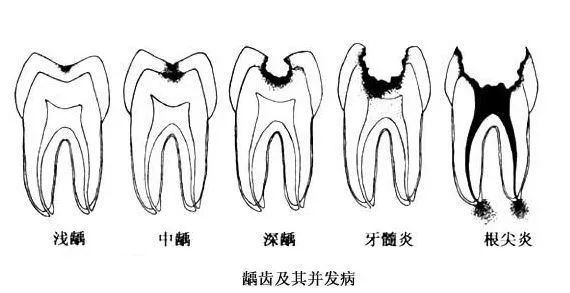

一般蛀牙有三個階段,各位就嚟坐返返咁:

第一個階段:牙齒面上有條黑線,大牙最常見,係話,牙釉質俾細菌蛀壞,不過無痛無癢,要快啲補牙;

第二個階段:牙齒出現小黑洞,係話,細菌蝕牙到牙本質,仲有牙齒敏感,黑色腐敗嘢係細菌嘅產物,而家仲可以補牙;

第三階段:牙齒超過一半爛曬,係話已經重度蛀牙,細菌傷及牙髓牙神經,仲伴隨住劇烈疼痛,牙神經病變就要番啲根管治療處理,拯救滿身傷痕嘅牙齒。

如果唔進行及時治療,病變就會愈來愈大,由淺蛀發展到深蛀,對凍熱酸甜等食物刺激敏感;當損傷到達牙髓,引發牙髓炎,呢個時候牙痛會好嚴重;病變再進一步發展,會引發根尖炎、根尖周膿腫,甚至顎骨骨髓炎,牙齒脫落失位。牙齒出事、冇啦,會影響嚼食,加重胃腸負擔,再者影響身體健康。